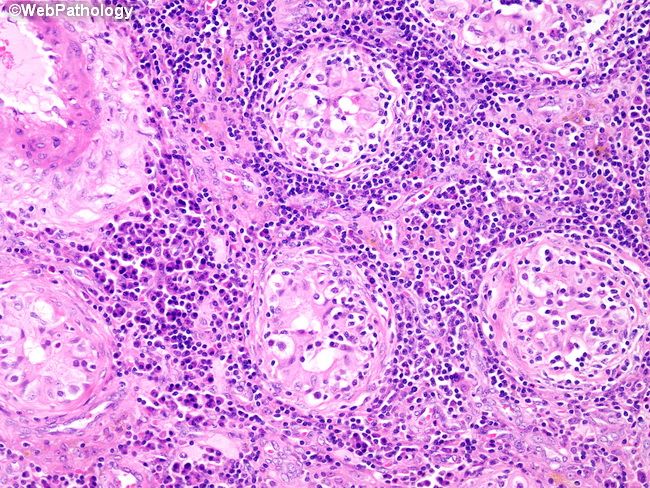

Паротитный орхит

Паротитный орхит 116 фото